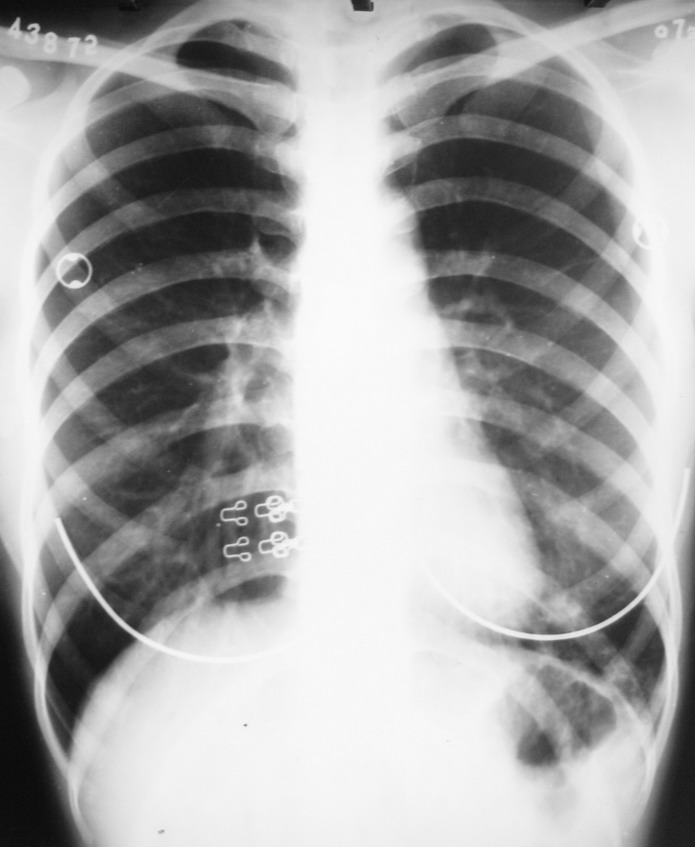

患者 女 22岁 咳嗽 咳痰 体温37.4度 白细胞在正常范围 于十日前诊断左肺下炎症 在个体诊所抗炎治疗9日 用药不详(未做过敏实验)今日复查 该患半年前曾在外院诊断过左肺下炎症 后治愈 该患者体质瘦弱

十日前片:

今日复查片:

左肺下野病灶有增多。考虑结核可能性。

考虑左下支扩伴感染

考虑:结核>炎症. 混合感染可能性大.

支气管扩张并肺部感染可能性大,建议ct检查。

似见囊样透亮影,考虑支扩并感染,不排除用药不规则而加重,若体质差也可没有中毒反应,还有痰的性状很重要

“半年前在外院”诊断左下肺炎,现又复发,白细胞在正常范围内,近十日不病灶有进展改变。考虑左下感染性病变,另照个左侧位片定位,如是下叶背段考虑结核可能性大。最终还是生化和治疗追综。